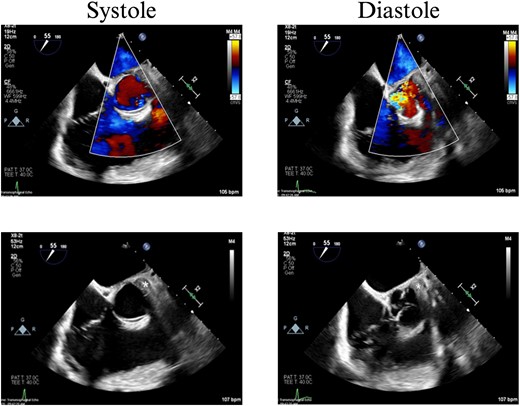

On hospital Day 7, the patient had acute hypoxic respiratory failure. CT chest found a right segmental pulmonary embolism and a retained bullet near the aortic root. A TEE was repeated, this time demonstrating severe aortic insufficiency (Fig. 4), and a bullet in the left coronary cusp. Cardiothoracic surgery was consulted for evaluation and management. The next day, the patient went to the OR for median sternotomy, cardiopulmonary bypass, aortic root repair with patch, re-attachment of the left coronary cusp, and removal of the bullet from the aortic root.

TEE with intracardiac bullet, severe aortic insufficiency. The bullet is labeled by an asterisk, with shadow artifact posterior to the bullet.